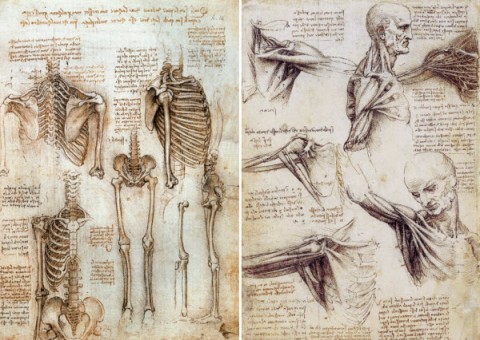

۱- آناتومی انسان، طراحی توسط لئوناردو داوینچی، بین سال های ۱۵۰۹ تا ۱۵۱۰: در زمانه ای که کمتر کسی به صورت روشمند درون و برون بدن انسان را مورد بررسی قرار داده بود، هنرمند دوره رنسانس -لئوناردو داوینچی- دست به کار شد و ۲۰۰ طراحی از سیستم اسکلتی و ماهیچه ای بدن انسان کشید. این تصاویر نه تنها زیبا هستند، بلکه در زمره دقیق ترین طراحی های انجام شده از بدن انسان، در اروپا، تا آن دوره زمانی هم قرار دارند.